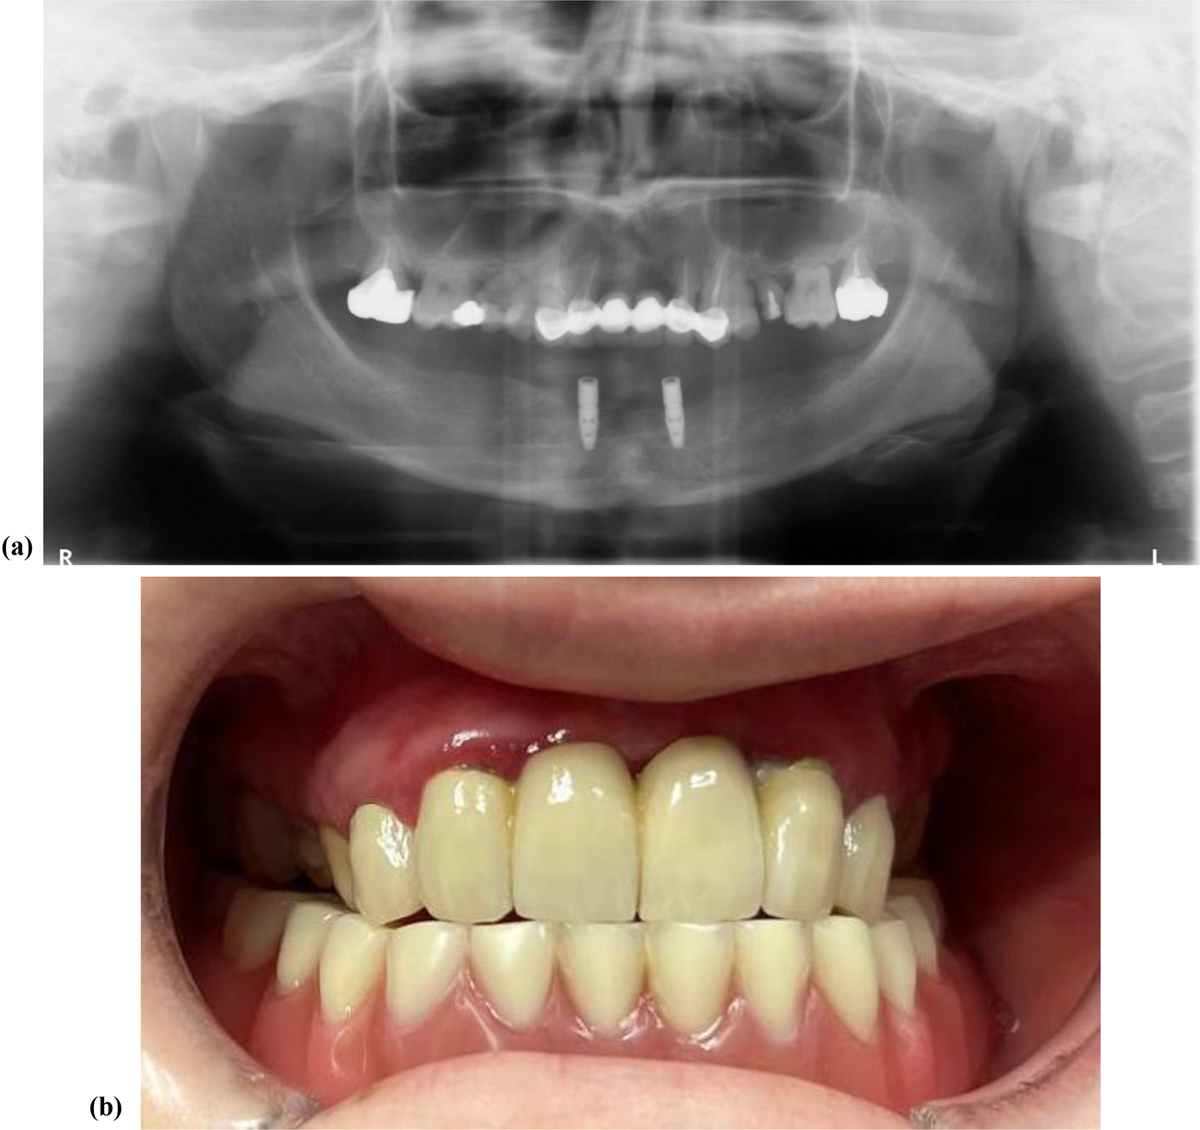

(A) Post-operative panoramic radiograph (June 2025) of case 1 after extractions and placement of two mandibular implants with Locator® attachment system. (B) Intraoral view in occlusion showing the maxillary bridge and mandibular overdenture on Locator® attachments.